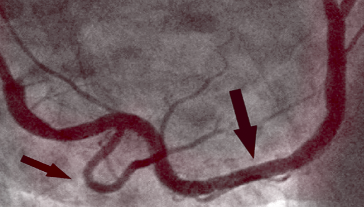

PO TERAPII

Na fotografii vpravo vidíme čistou pravou koronární tepnu, již bez stop zkalcifikované aterosklerotické plaky u stejného pacienta po jednom měsíci terapie. Nejsou zde žádné smrtící cholesterolové usazeniny. Krev proudí volně a zásobuje kyslíkem všechny orgány.